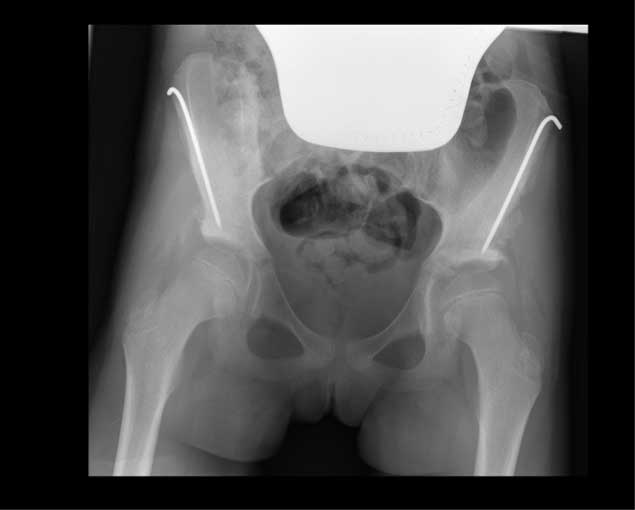

Durch das

Einbringen eines Knochenspans (mit Drähten fixiert) konnte das Pfannendach auf beiden Seiten wieder

in die normale Position gebracht werden. Der Draht wird später in einem kleinen Eingriff wieder

entfernt.

Durch das Einbringen eines Knochenspans konnte das Pfannendach auf beiden Seiten wieder in die normale Position gebracht werden. Der Draht wird später in einem kleinen Eingriff wieder entfernt.